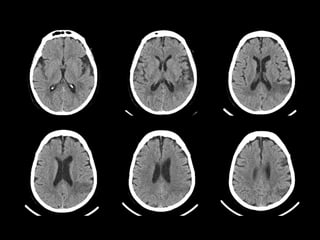

 Mr. LR a 80 ans, masculin se présente

 Une historie de délire qui dure 3 mois

Une historie de délire qui dure 3 mois

 Il est récemment tombé du lit

Il est récemment tombé du lit

 Une plaie du scalp

 Pas de déficit neurologique focal

 Un Scanner cérébral non injecté est

Analyse

 Pouvez vous voir les anomalies?

 Quel est votre impression?

 Quel serai votre prémier diagnostic?

Cas Bonus - Answer

 Mr. LR a eu un petit

hématome sousdural

sousdural gauche

 Le sang est vu le long de

l’espace sous dural gauche et

aussi dans la partie antérieure

de la faux du cerveau

(Fleches)

 L’hématome est

L’hématome est aigu

 A cause de sa petite taille,

aucun traitement n’a été

necessaire

 Les Scanner de suivi ont

montré une resorption de

montré une resorption de Scanner normal pour la comparaison